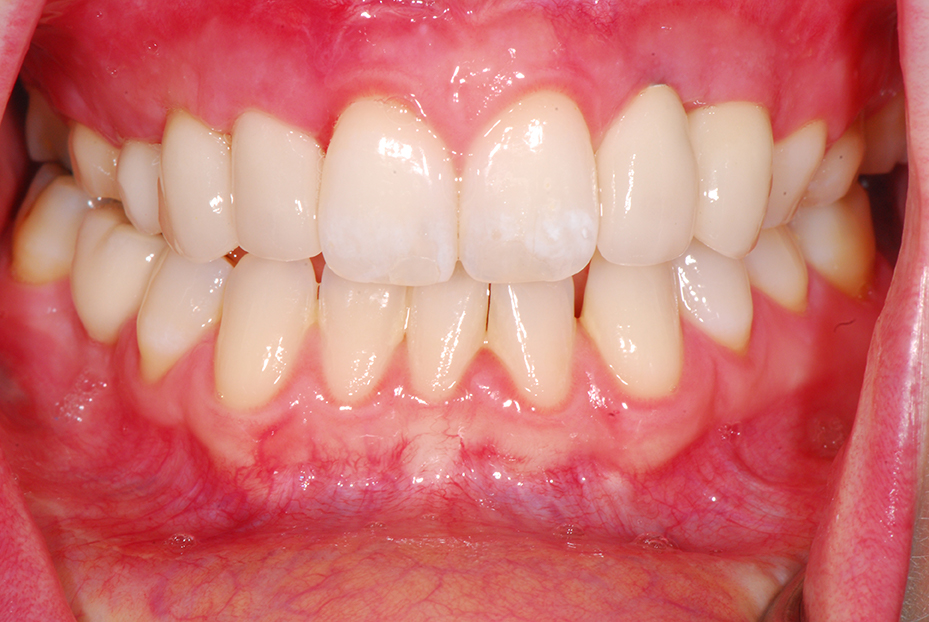

Orthodontic closure of the front gap and replacement of the loose baby teeth with some permanent implant crowns and bridgework.

After